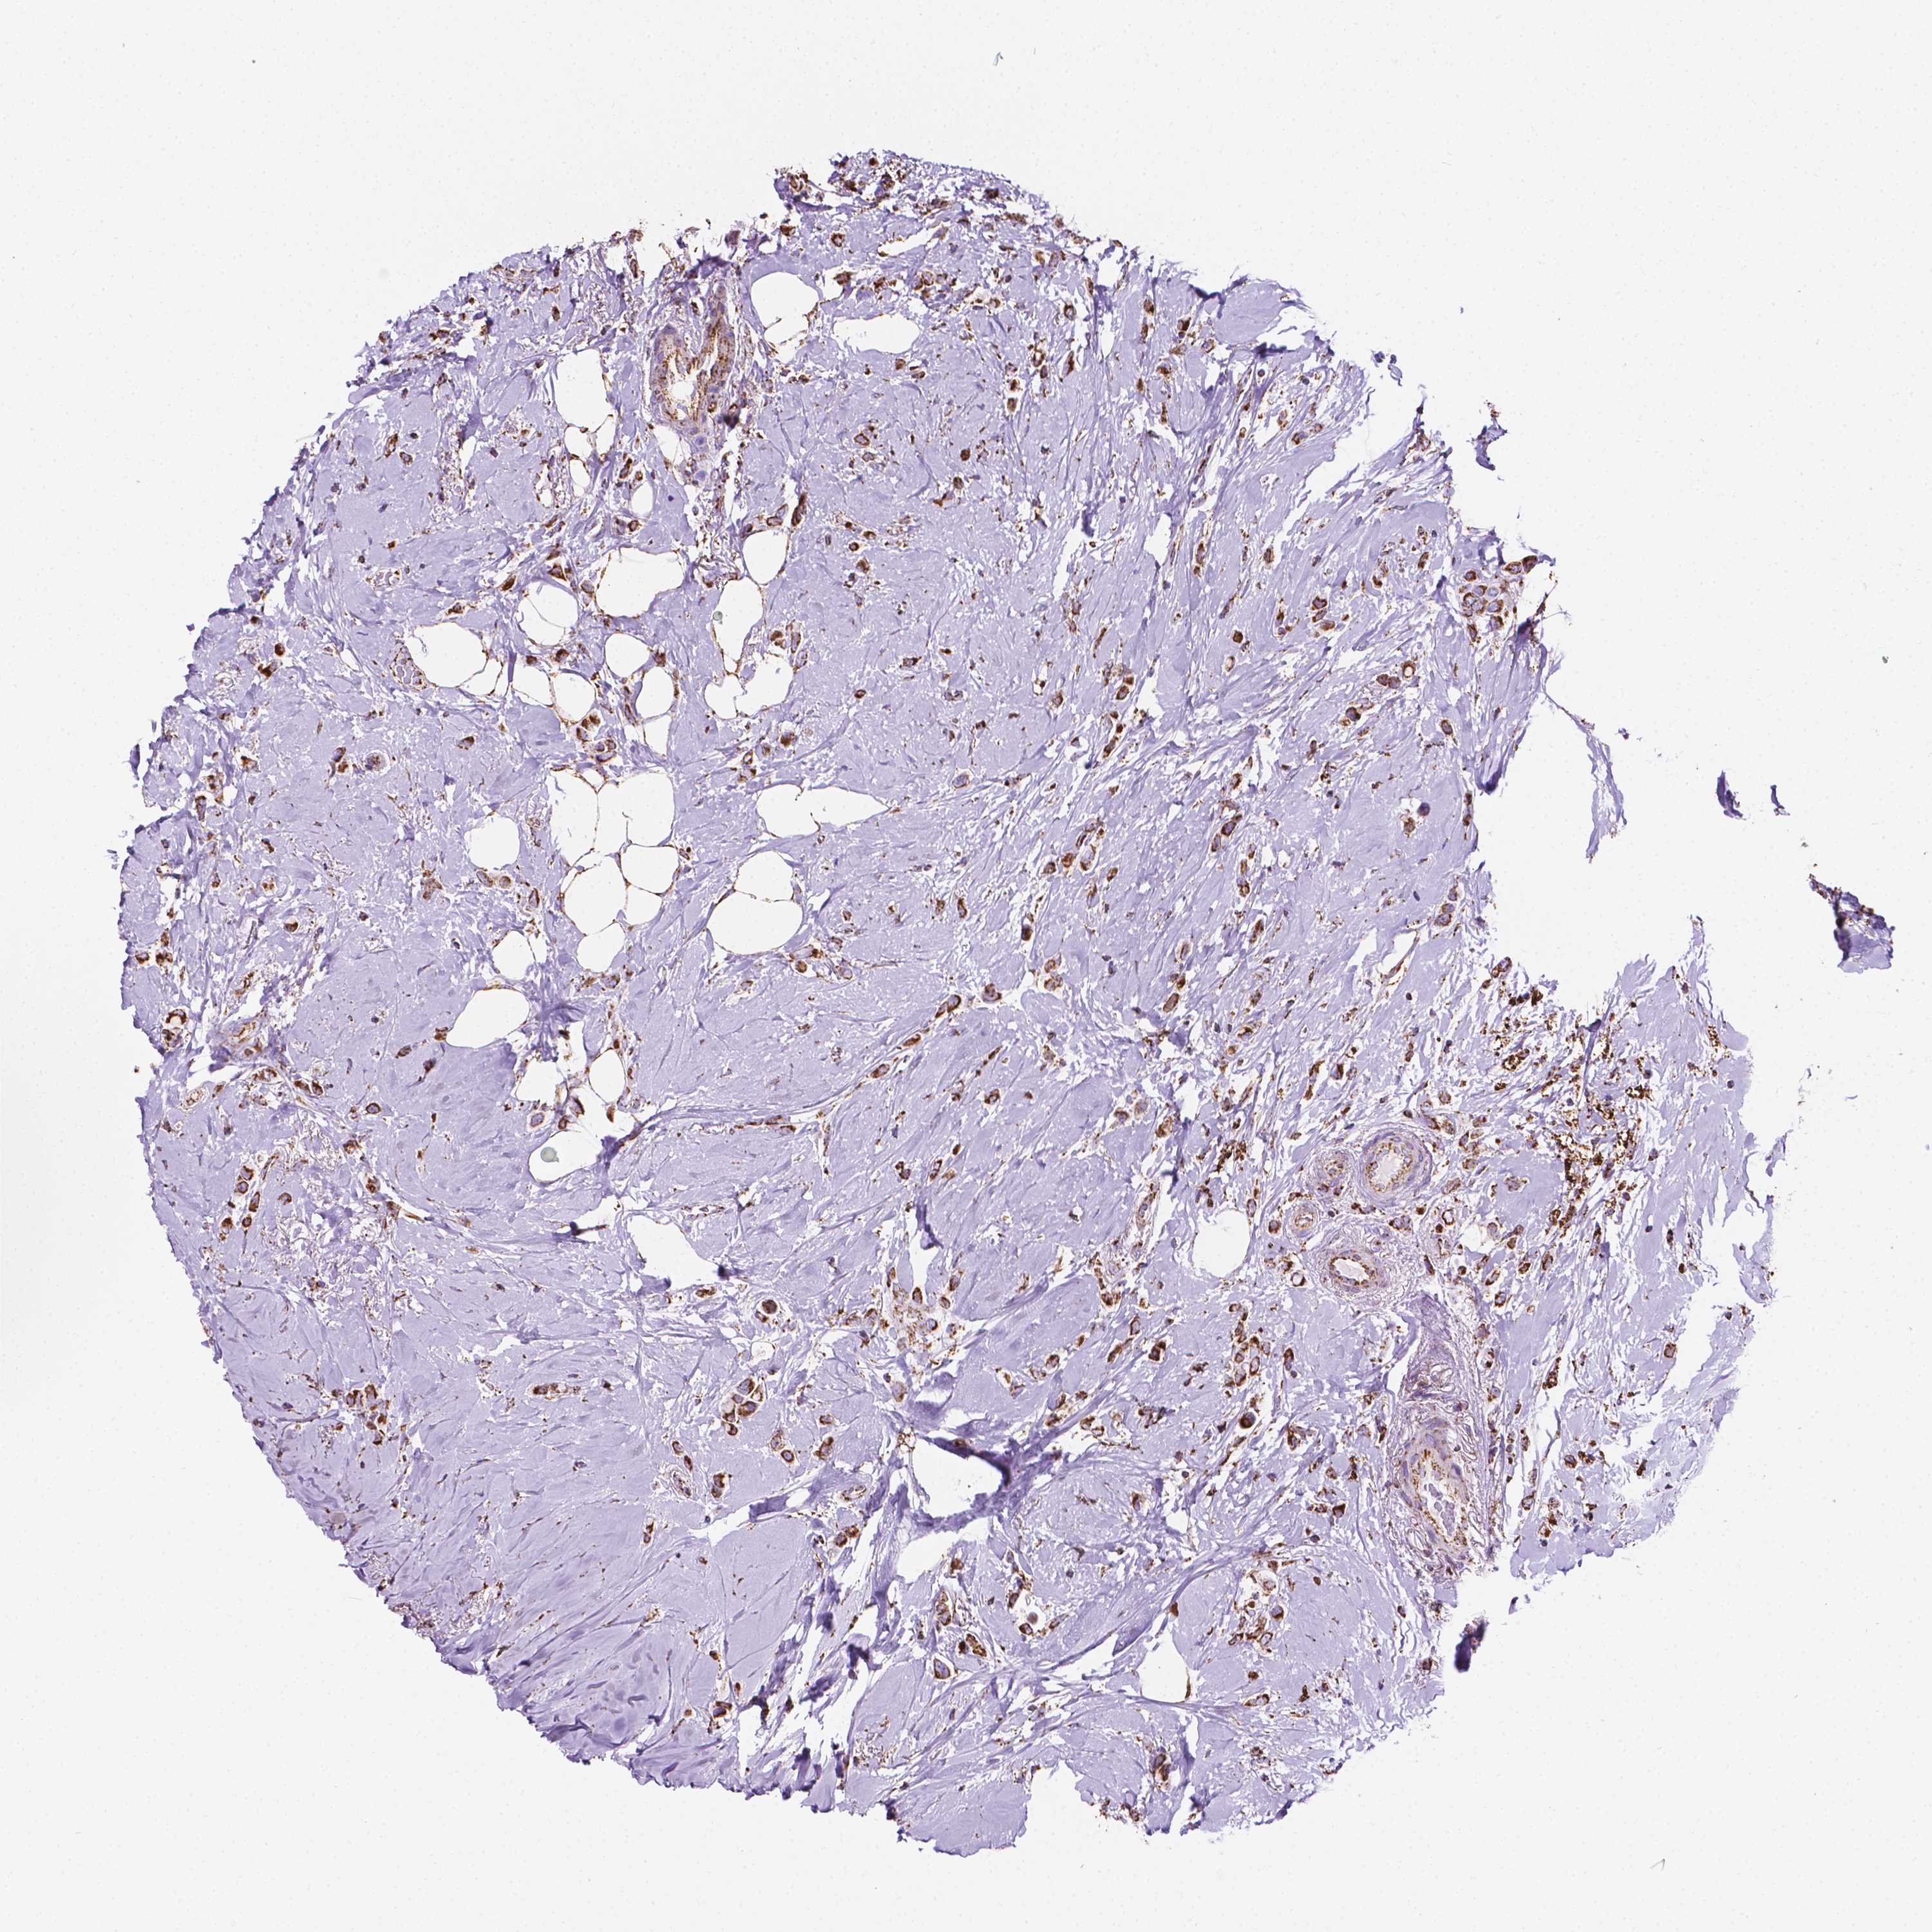

CANCER BREAST CANCER Show tissue menu

BRCA TCGA BRCA VALIDATION PROTEIN EXPRESSION

Breast cancer

Human cancer

RMDN3 is not prognostic in Breast Invasive Carcinoma (TCGA)